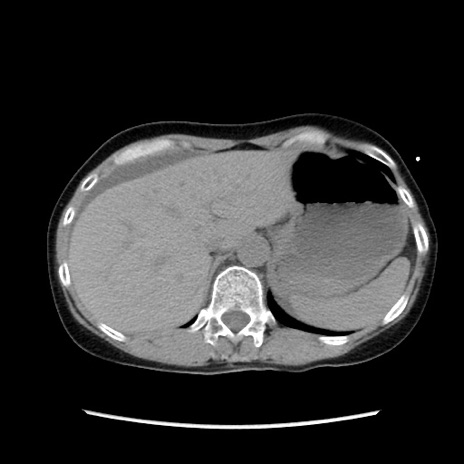

症例32(横断像)

【症例】40歳代 女性

【主訴】上腹部痛、嘔気・嘔吐

【現病歴】約9時間前頃から急に上腹部痛、嘔気、嘔吐が出現。改善しないため救急要請。

【既往歴】子宮頚癌(広汎子宮全摘術、放射線療法)、腸閉塞

【身体所見】腹部:平坦、軟、腸雑音亢進、上腹部を中心に腹部全体に圧痛あり。

【データ】WBC 8400、CRP 0.03